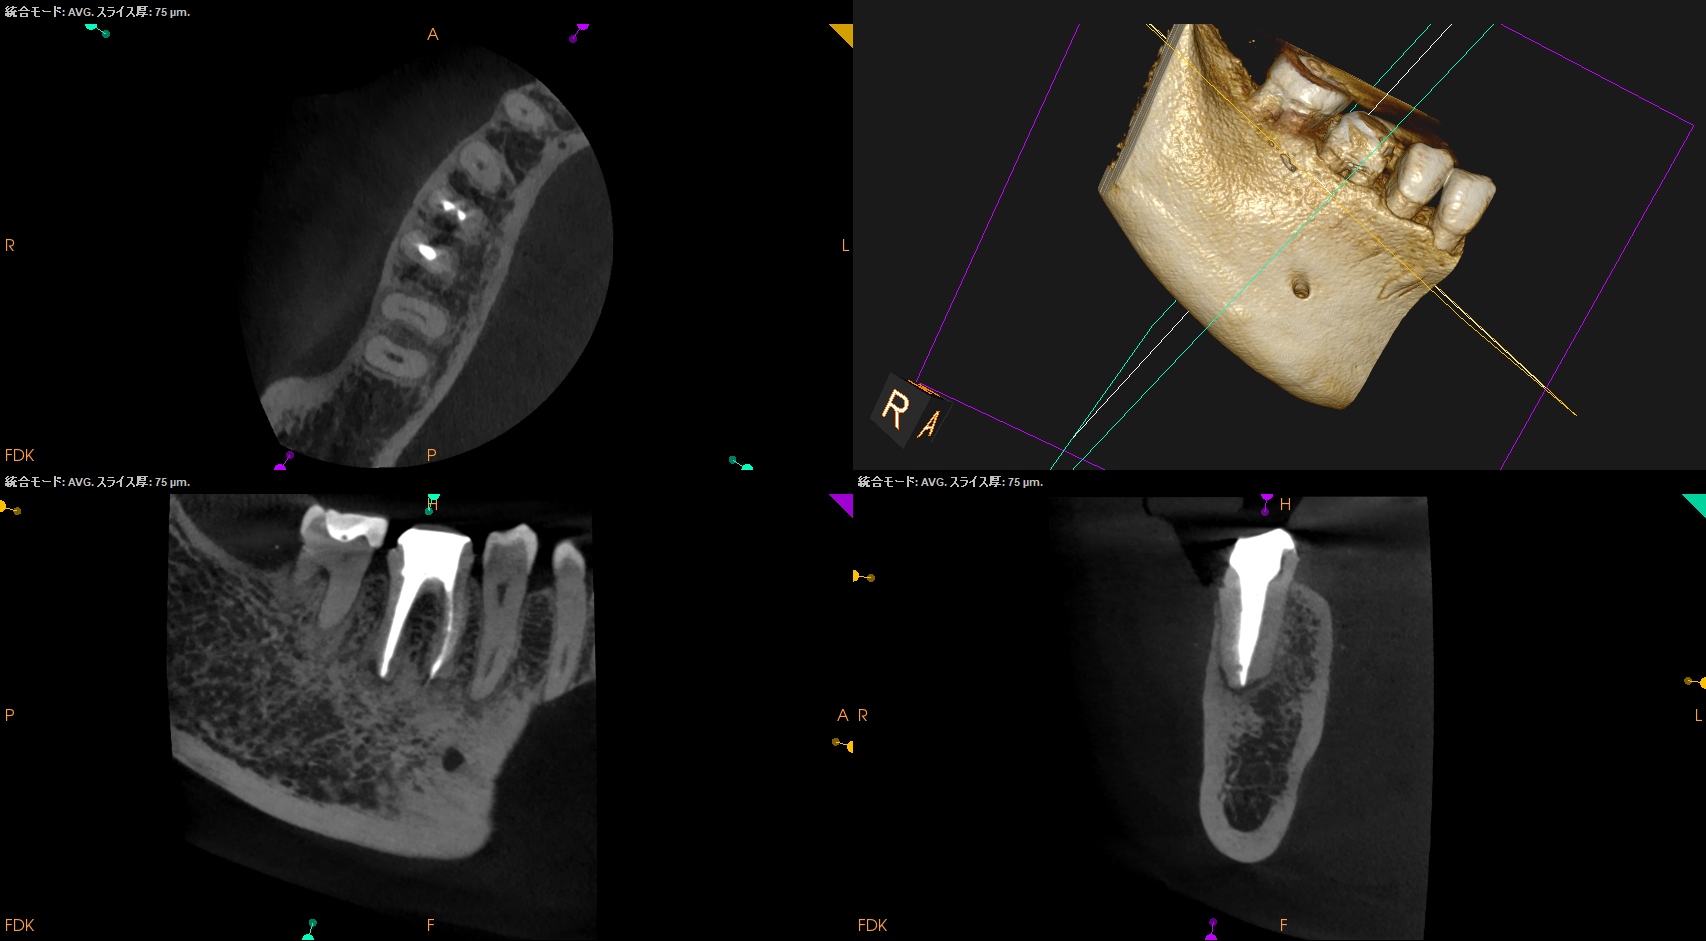

CBCT(2025.8.29)

#30

MB

ML

D